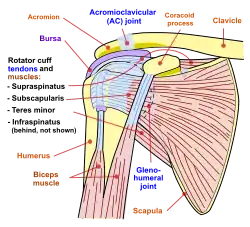

The intrinsic muscles of the scapula include the muscles of the rotator cuff(SITS muscle)—the subscapularis, supraspinatus, infraspinatus and teres minor.[3] These muscles attach to the surface of the scapula and are responsible for the internal and external rotation of the shoulder joint, along with humeral abduction.

The extrinsic muscles include the biceps, triceps, and deltoid muscles and attach to the coracoid process and supraglenoid tubercle of the scapula, infraglenoid tubercle of the scapula, and spine of the scapula. These muscles are responsible for several actions of the glenohumeral joint.

Diagram of the human shoulder joint, front view

Diagram of the human shoulder joint, front view -